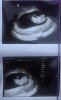

Dziewczynki to moje maleństwo. Ma 2,5 cm

Na usg super było widać jak rusza nóżkami i rączkami ❤ cudowne chwile popłakałam się..

Jedyny plus taki, ze na prenatalne mogę przyjść z narzeczonym, no i ze widziałam maleństwo. Widziałam dziewczyny, ze u was po wizycie zmienił się termin porodu, pewnie z usg. Mi nic nie powiedział